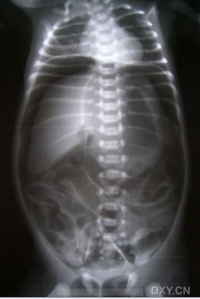

胃肠道穿孔的主要X线表现是气腹即腹膜腔内出现游离气体。关于气腹的显示方法,一般是采用透视与照片检查。尤其是少量气腹的显示则尤为重要,如病情允许,立

位透视并转动体位观察,此时往往能显示膈下新月形的游离气体的存在,因为气体总是具有浮游到腹腔最高处去的倾向,确定了膈下游离气体后,应即时照片以供临床参考。

四、鉴别诊断[编辑 | 编辑源代码]

胃肠道穿孔引起的气腹需与正常解剖变异间位结肠鉴别。透视下转动体位可以鉴别。

胃肠道穿孔的传统诊断方法为摄取腹部X线平片,观察膈下、腹壁下有无游离气

体,以此作为主要诊断依据,但是准确性有限。